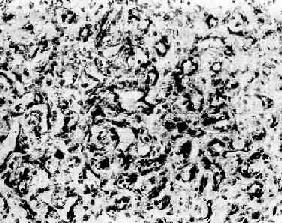

图7-15 纤维

组织由分化良好的纤维细胞构成,呈编织状排列,有丰富的胶原纤维